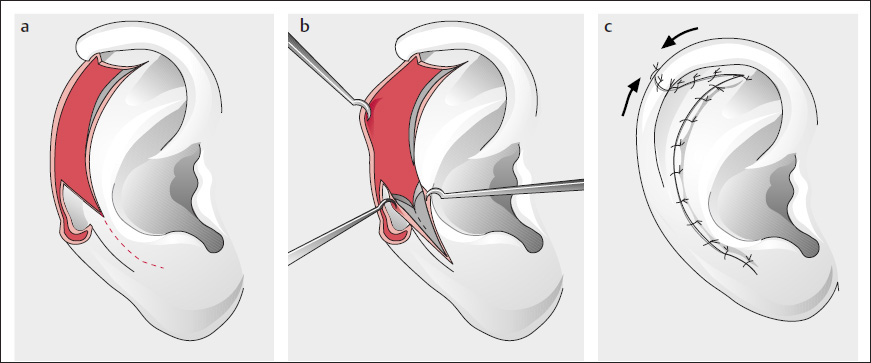

Antia and Buch’s Modification with Mobilization of the Helical Crus

( Fig. 10.25 ; Antia and Buch 1967, Antia 1974)

In a modification for larger defects, the helical crus was additionally incised (it remains pedicled posteriorly and superiorly).

Similar to Antia and Buch (1967) and Antia (1974), and in contrast to Gersuny (1903; see Fig. 10.23 ), we made only a two-layer, crescent-shaped excision in the scapha after excision of the tumor and dissected the skin on the posterior auricular surface ( Fig. 10.24b, d, e ).